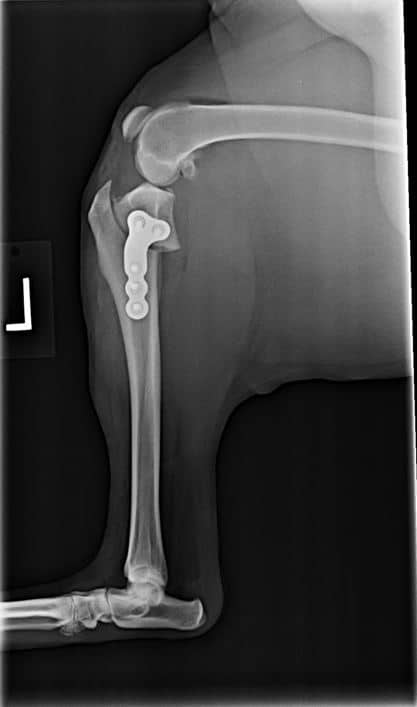

TPLO (Tibial Plateau Leveling Osteotomy) is a specialized surgical procedure designed to stabilize the knee joint in pets, particularly dogs, that have suffered a torn Cranial Cruciate Ligament (CCL). This surgery alters the angle of the tibial plateau, effectively removing instability and allowing your pet to regain mobility. During the procedure, a bone plate and surgical screws are used to secure the newly adjusted angle, eliminating the need for the damaged CCL.

Pets with a torn Cranial Cruciate Ligament often experience concurrent injuries, such as meniscus damage. The TPLO surgery involves a thorough exploration of the entire joint, ensuring that all injuries are identified and treated during the operation. TPLO is a widely recommended solution for dogs with CCL injuries, helping them return to an active and pain-free life.

After TPLO